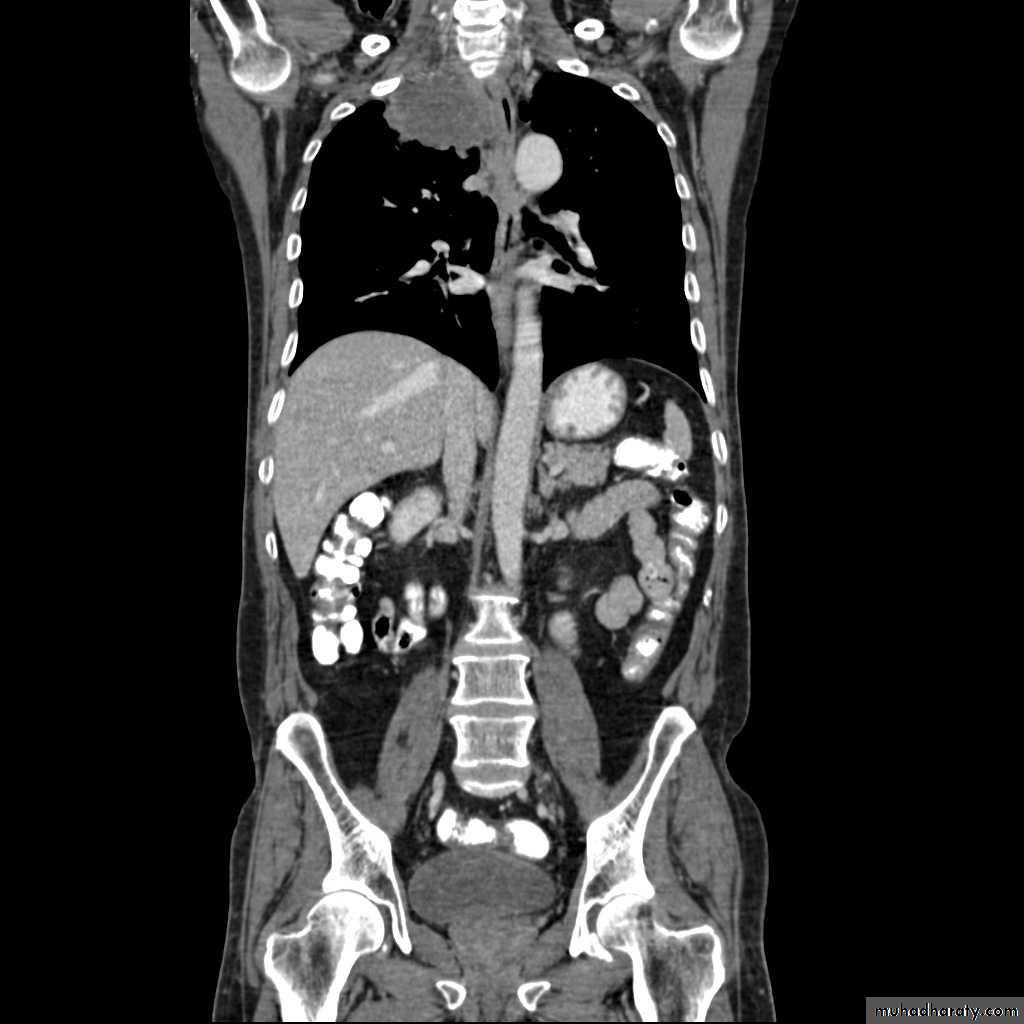

Hydatid cysts result from infection by the Echinococcus, and can result in cyst formation anywhere in the body. Humans are accidental host and the infection occurs by ingesting food contaminated with Echinococcus eggs ,Pulmonary hydatid infection is a common manifestation of hydatid disease.The lung is the second most common site of involvement with echinococcosis granulosus in adults after the liver (10-30% of cases), and the most common site in children. The coexistence of liver and lung disease is present in only 6% of patients .

Chest XR features include :

Non-complicated hydatid

multiple or solitary rounded opacity

diameter of 1-20 cm

unilateral or bilateral

predominantly found in the lower lobes